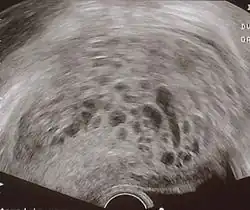

The diagnosis is strongly suggested by ultrasound (sonogram), but definitive diagnosis requires histopathological examination. On ultrasound, the mole resembles a bunch of grapes ("cluster of grapes" or "honeycombed uterus" or "snow-storm").[14] There is increased trophoblast proliferation and enlarging of the chorionic villi, and angiogenesis in the trophoblasts is impaired.[15]